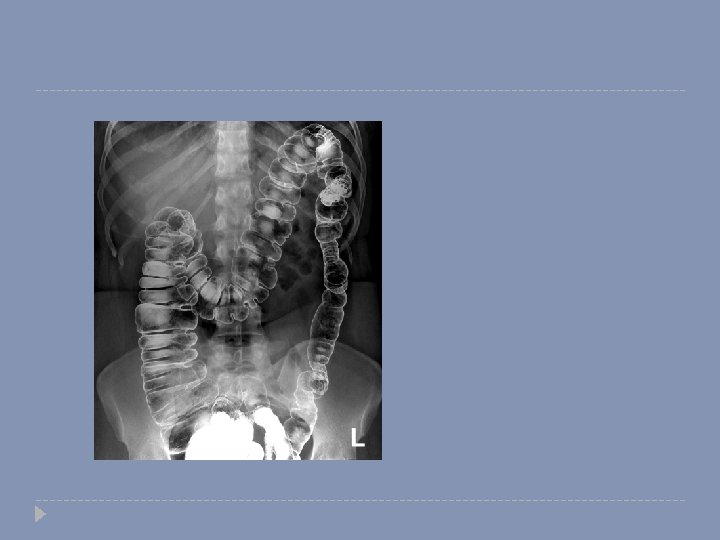

Floruscopy � We are using a contrast material for better visualization of hollow organs, such as bowel loops and KUB. � It is useful to assess the mucosal pathology. � We � If can use either oral or rectal contrast we use rectal contrast; we can use either: � Single contrast barium enema. � Double contrast barium enema.

Small bowel contrast study (enema)